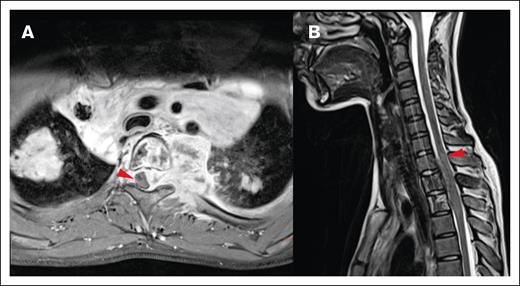

Most CNS lesions demonstrated an adequate metabolic response at IRA, with 89.1% PET negative (Deauville score 1-3) and 10.9% remaining PET positive (Deauville score 4 or 5; Figure 6). Only 1 of the CNS lesions that remained PET positive at IRA was irradiated, and none of these lesions were sites of relapse. Two CNS lesions (3.6%) that were PET negative at IRA (Deauville 1 and 3) were associated with relapse, and neither received irradiation. Thirteen CNS lesions (23.6%) in 13 patients received irradiation, and none were sites of disease relapse. These results have been summarized in Figure 7.

Staging and response assessment. Imaging at staging shows a large paraspinal mass (A, MRI) with intense glucose metabolism (B, 18F-FDG-PET/CT; red arrows = lymphoma; white arrows = normal kidneys). The mass originates from the bone and extends into the neuroforamen and the spinal canal (A-B). After 2 courses of OEPA chemotherapy, 18F-FDG-PET shows a good metabolic response (C, maximum intensity projection; red circle surrounds the slight residual uptake of the former CNS lesion; [D-E] 18F-FDG-PET/CT; same height as panel B; minimal glucose metabolism within the residual mass [red arrows]).